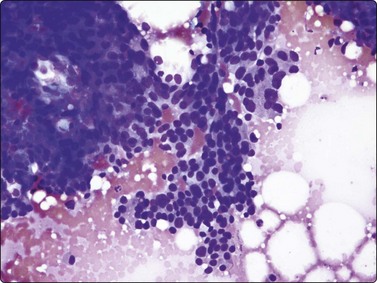

Breast tissue in pregnancy and lactation (Fig. 7.8)

image image image

Fig. 7.8 Lactating breast

Dispersed acinar cells with abundant pale and fragile cytoplasm, rounded nuclei and prominent central nucleoli; background of lipid secretions (A, MGG, HP; B, H & E, HP oil); (C) Corresponding tissue section (H&E, IP).

Criteria for diagnosis

Cellular smears,

Poorly cohesive, mainly dispersed epithelial cells of acinar type,

Cells have abundant fragile cytoplasm with secretory vacuoles and frayed borders,

Rounded vesicular nuclei and central nucleoli,

Dirty background due to lipid secretion and stripped nuclei with prominent nucleoli,

Single bipolar nuclei difficult to find.

FNB is very useful in reducing surgical intervention to a minimum during pregnancy and lactation. The pattern seen in FNB smears of ‘lumps’ in a pregnant or lactating breast can be problematic to inexperienced eyes and cause concern for malignancy.93,94 Smears are usually cellular. The cells are enlarged and arranged in loose groups or singly. The cells have an abundant fragile cytoplasm, vacuolated and finely granular. Nuclei are round, central, larger than the usual ductular cells, and have distinct small nucleoli (Fig. 7.8B). Some epithelial nuclei are stripped of cytoplasm. Single naked bipolar/oval nuclei are difficult to find. The background of abundant milky secretion with numerous lipid droplets seen as vacuoles is characteristic of actively secreting breast tissue and is the main clue to the diagnosis (Fig. 7.8A).